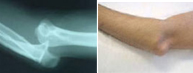

This type of dislocation occurs most frequently in the second decade of life. The separation between the arm and forearm is common in sports, especially sports that may cause impact on the hand with the elbow in extension.

The injury not only affects the bone but the ligamentous and neurovascular structures so it requires a careful exam in the emergency room to diagnose the degree of impairment and proper treatment.

Relocation of the elbow into its anatomic position is essential through a gentle traction that sometimes may need general anesthesia. There are cases that joint congruity after the reduction of the dislocation is not maintained (unstable joint) and it may be necessary to reinforce the joint stability with surgery.